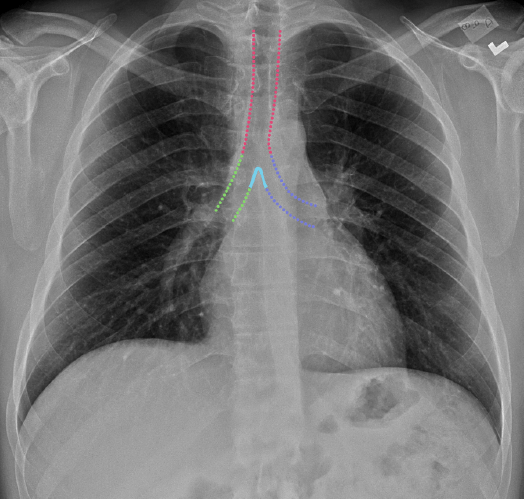

Labelled radiographs and CT/MRI series teaching anatomy with a level of detail appropriate for medical students and junior residents.

Chest

Chest

Chest radiograph & CT anatomy

Chest

Chest

Chest radiograph & CT anatomy